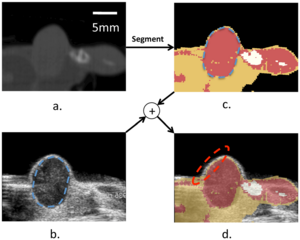

- 7.4 An Open Environment CT-US Fusion for Tissue Segmentation During Interventional Guidance